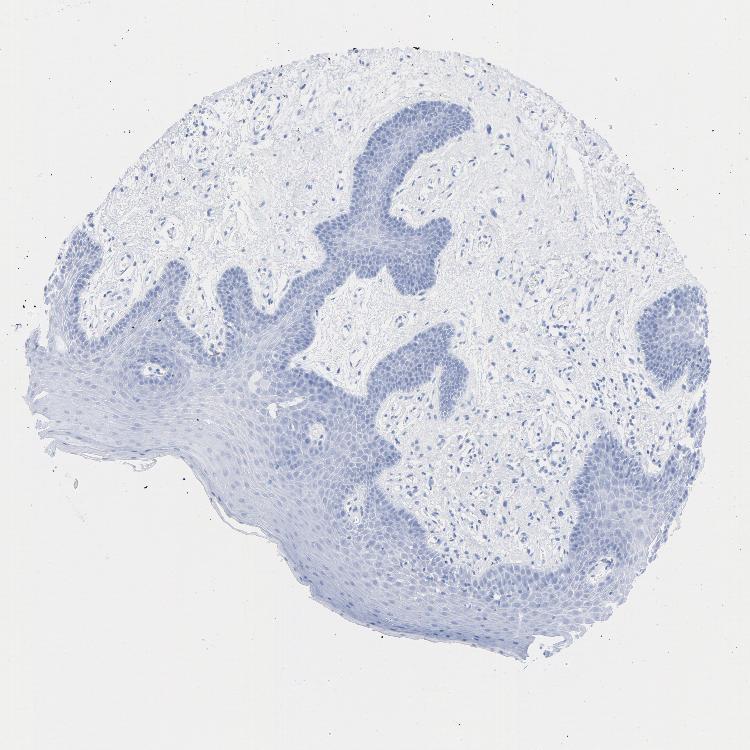

TISSUE PRIMARY DATA ORAL MUCOSA Show tissue menu

ORAL MUCOSA - Antibody stainingi

Antibody staining in the annotated cell types in the current human tissue is reported as not detected, low, medium, or high, based on conventional immunohistochemistry profiling in selected tissues. This score is based on the combination of the staining intensity and fraction of stained cells.

Each image is clickable and will lead to virtual microscopy that enables deeper exploration of all samples and also displays staining intensity scores, fraction scores and subcellular localization as well as patient and tissue information for each sample.

Antibody HPA052625Antibody CAB004300Antibody CAB004674

Squamous epithelial cells HighNot detectedLow